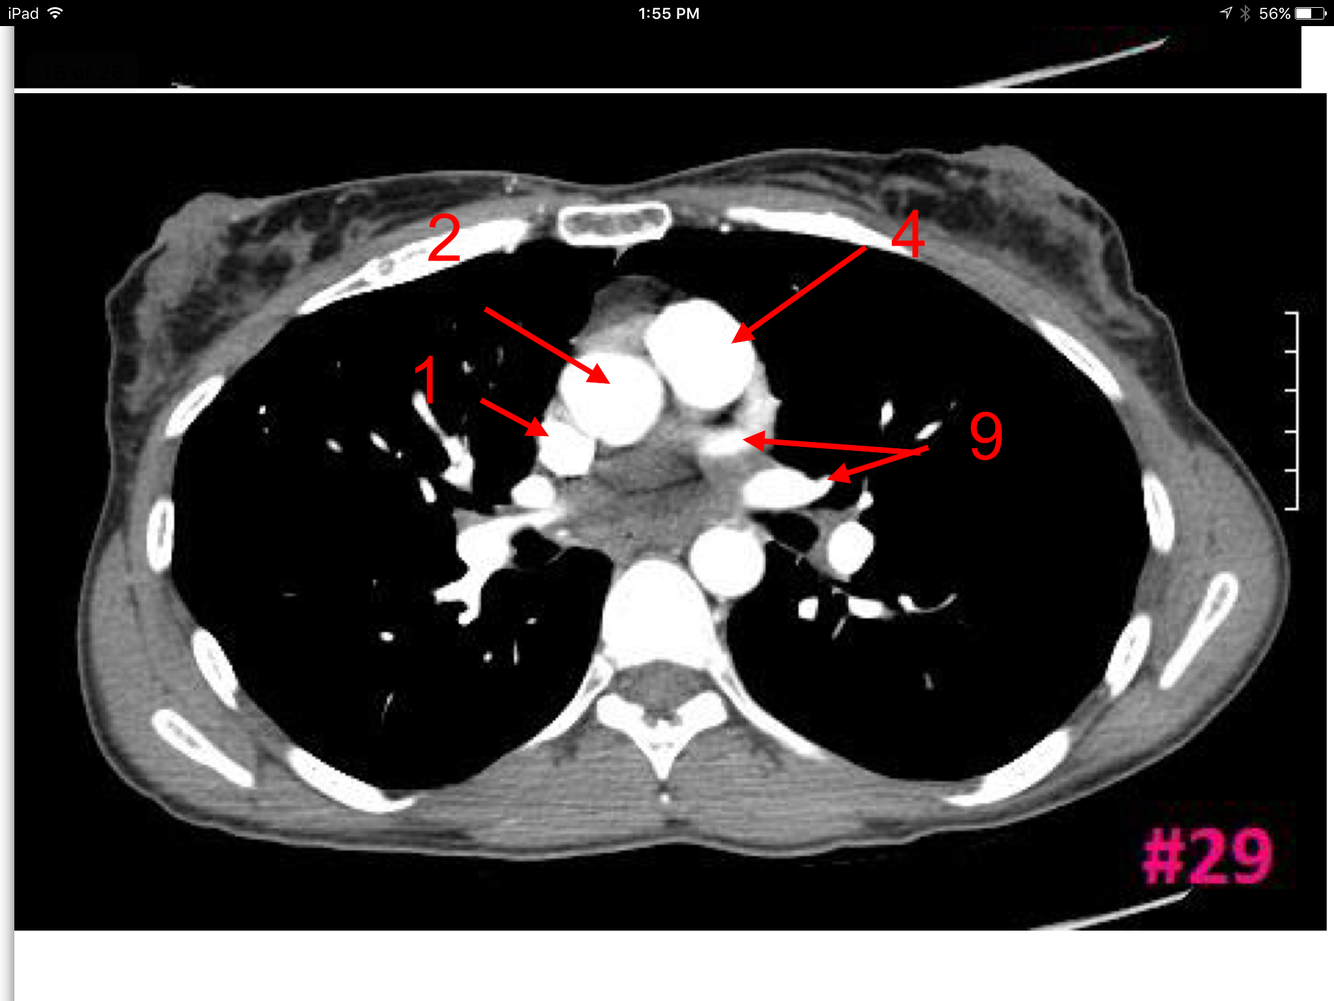

15

Q

A

Superior vena cava

Ascending aorta

Descending aorta

Lt pulmonary artery

Lt main bronchus

Rt main bronchus

Rt pulmonary artery

Rt intervertebral foramen

How well did you know this?